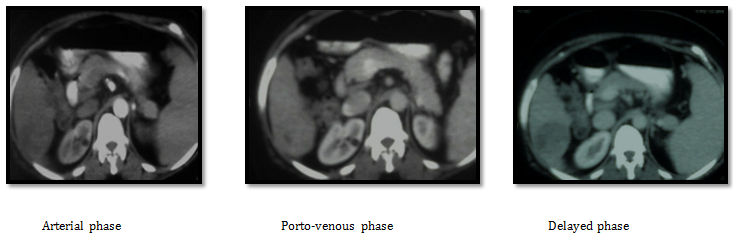

Case number (2): A 50years old male patient known to have hepatitis C virus with right hepatic lobe HCC of about 5.5 cm by triphasic CT scan. His laboratory tests was as follow AFP 6.3 IU/ML, ALT 94, AST 72, Direct Bilirubin 2, Albumen 3.2g/dl, Creatinine 0.9) with normal CBC , PC 65%, INR 1.3).

CT images before doing any procedure: His CT showing right hepatic lobe segment VIII well defined focal lesion of about 5.5cm very close to the right portal vein branch with early nodular enhancement in arterial phase and rapid wash out in delayed phases, mild splenomegaly and no ascites. We decided to start by RF ablation (Figure 7).

Figure 7 CT Images before doing any procedure.

CT images after three weeks from RF ablation: Post RF CT showing partial about 50% ablation of the lesion with residual tumoral reactivity and newly developed intra-lesional portal shunts. Then we decided to complete treatment by TACE after one month from RF ablation. 1st we did angiography that revealed right hepatic artery superior branch small aneurysmal dilatation (pseudo-aneurysm), that is appears after RF ablation. It was affecting the flow as seen in next images (Figure 8). So we decided to embolize the aneurysm and correct the flow into the tumoral tissue as seen in the following images (Figure 9). Lastly we injected the chemo-lipiodol mixture into the right lobe lesion (Figure 10).

Follow up by triphasic CT after 3 months of combined therapy showing: Good uptake of lipiodol droplet by all residual tumoral tissues with small segment VIII residual active lesion that were noticed and treated by another session of TACE after one month (Figure 11). After 8 month patient developed two new left hepatic focal lesions and small satellites around the 1st ablated one with mild elevation of AFP reaching 50IU/DL that is further retreated by TACE. After 12month patient follow up showing no newly developed lesions with AFP reaching 25 IU/DL (Figure 12).